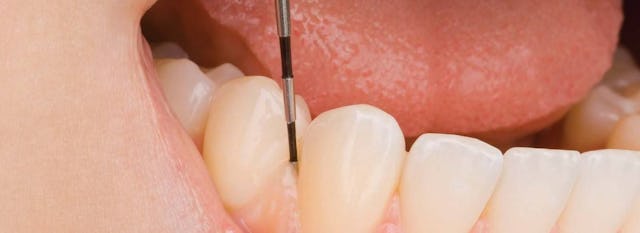

Wie schwer die Parodontitis wirklich ist, stellt man am besten mit der sogenannten Taschentiefenmessung fest (siehe dazu Kapitel „Tasche“).

Die Taschenmessung mit der Parosonde sieht zwar gfürchig aus, tut aber praktisch nicht weh, und ist ein sehr wichtiges Diagnostikum um die Gesundheit des Zahnhalteapparates zu befunden.

Messung der Taschentiefe

Zur Diagnostik der parodontalen Erkrankungen gehört zuallererst das Bestimmen der Taschentiefe. Hier auf dem Bild wird die Taschentiefe (sog. Parodontalbefund) mit einer Parodontalsonde bestimmt. In der Regel werden vier verschiedene parodontale Befunde unterschieden.

1. Kleiner, schneller Parodontalbefund, um sich einen ersten Überblick zu verschaffen.

2. Parodontalbefund mit Taschentiefebestimmung bei einem Patienten mit geringem Taschenbefall.

3. Parodontalbefund mit Taschentiefebestimmung bei einem Patienten mit mittlerem Taschenbefall.

4. Parodontalbefund mit Taschentiefebestimmung bei einem Patienten mit grossem Taschenbefall.